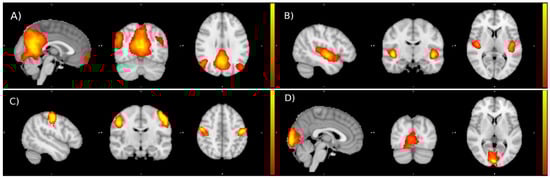

3.4. Preliminary Functional Connectivity Investigations after Cactus Pear Fruit Consumption

- Piccoli, T.; Maniaci, G.; Collura, G.; Gagliardo, C.; Brancato, A.; La Tona, G.; Gangitano, M.; La Cascia, C.; Picone, F.; Marrale, M.; et al. Increased Functional Connectivity in Gambling Disorder Correlates with Behavioural and Emotional Dysregulation: Evidence of a Role for the Cerebellum. Behav. Brain Res. 2020, 390, 112668. [Google Scholar] [CrossRef]